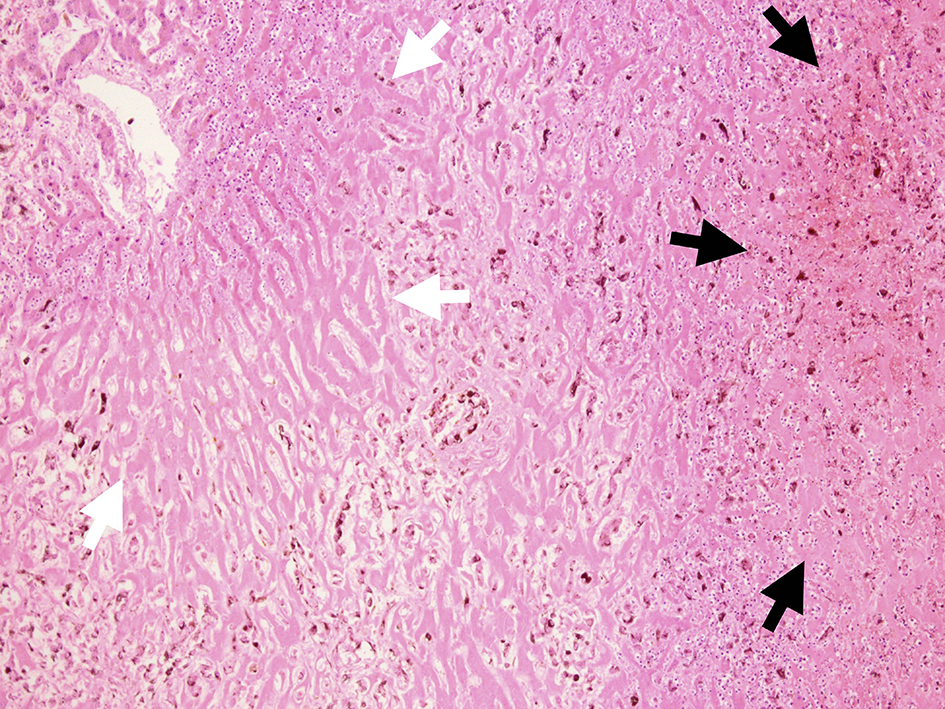

Microscopic examination of these organs revealed several interesting findings. Massive necrosis of normal hepatocytes and melanoma cells was observed in the liver. The lesion was composed of two parts: 1) centrilobular necrosis without bleeding; and 2) perilobular necrosis with hemorrhage (Fig. 7). Extensive necrosis was observed within the largest pulmonary tumor (Fig. 8), unlike the biopsied specimen taken antemortem (Fig. 9).

![]() Click for large image | Figure 7. Microscopic view of liver cut surface. Centrilobular necrosis without bleeding (white arrow) and perilobular necrosis with hemorrhage were shown (black arrow). Diffuse invasion of atypical melanocytes was observed. |